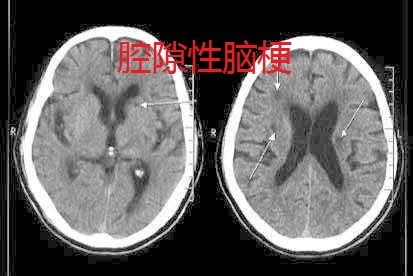

腔梗和脑梗有何区别

答:脑梗包括腔梗,腔梗是脑梗的一种类型。脑梗根据发病原因不同,临床上可以分为腔梗、脑拴塞、脑分水岭梗死和动脉粥样硬化血栓性脑梗死。腔隙性脑梗死一般是指大脑半球或

答:建议:这两者当然是不相同的,脑梗就是脑梗塞,腔梗就是腔隙性脑梗塞,脑梗塞一般可能导致偏瘫,严重的可能危及生命,腔梗一般没有明显的临床症状,不会危及生命。

答:1、腔梗是脑梗的一种,相对来说比较轻,它是堵塞比较小血管,检查时查LPA时,看人体内脂肪酶活性剂(LPA)高不高,如果高要进行治疗,维持比较稳定的水平,这样有利复恢。 2、

答:成为脑梗塞。 脑梗塞是缺血性中风的总称,包括脑血栓形成、脑栓塞、腔隙性梗塞等。 腔梗多发生在50岁以上的中老年人,由于梗死面积较小,临床症状较轻,如一侧面部和上下

答:成为脑梗塞。 脑梗塞是缺血性中风的总称,包括脑血栓形成、脑栓塞、腔隙性梗塞等 较大的梗塞,则可引起肢体的感觉和运动障碍。 腔隙性梗死,简称”腔梗”,是指颅内

答:成为脑梗塞。 脑梗塞是缺血性中风的总称,包括脑血栓形成、脑栓塞、腔隙性梗塞等。 较大的梗塞,则可引起肢体的感觉和运动障碍。 腔隙性梗死,简称”腔梗”,是指颅内直径

答:指导意见:你好!通过你的描述,你想能明白腔梗和脑梗的区别,腔梗就是腔隙性脑梗塞,脑深部穿通动脉闭塞引起的脑梗塞,经巨噬作用使留下梗塞灶直径小于2mm者,称为腔隙性脑

答:发病机制为血栓形成或栓塞,症状的性质因病变累及的血管不同而异。 脑梗塞是由于脑 脑腔梗 脑腔梗在临床上较为常见,就是通常所说的腔隙性脑梗塞,属于脑梗塞(脑血栓、